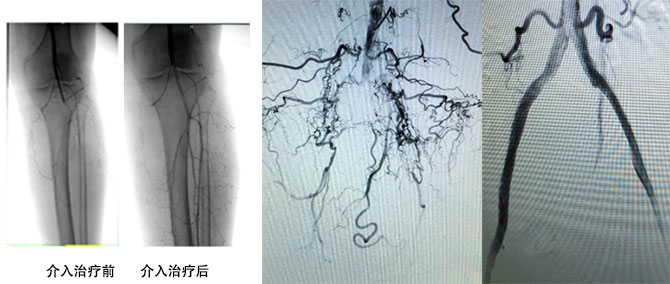

介入治疗